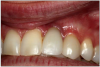

Dental Implants (Figure 12). Given that the anchoring of a dental implant is achieved by osseointegration, and smoking is a risk factor for the destruction of soft and hard tissue that support the teeth, it is agreed that smoking increases the risk of implant failure.2,8,35-38

Figure 12. Dental implants.

Figure 12